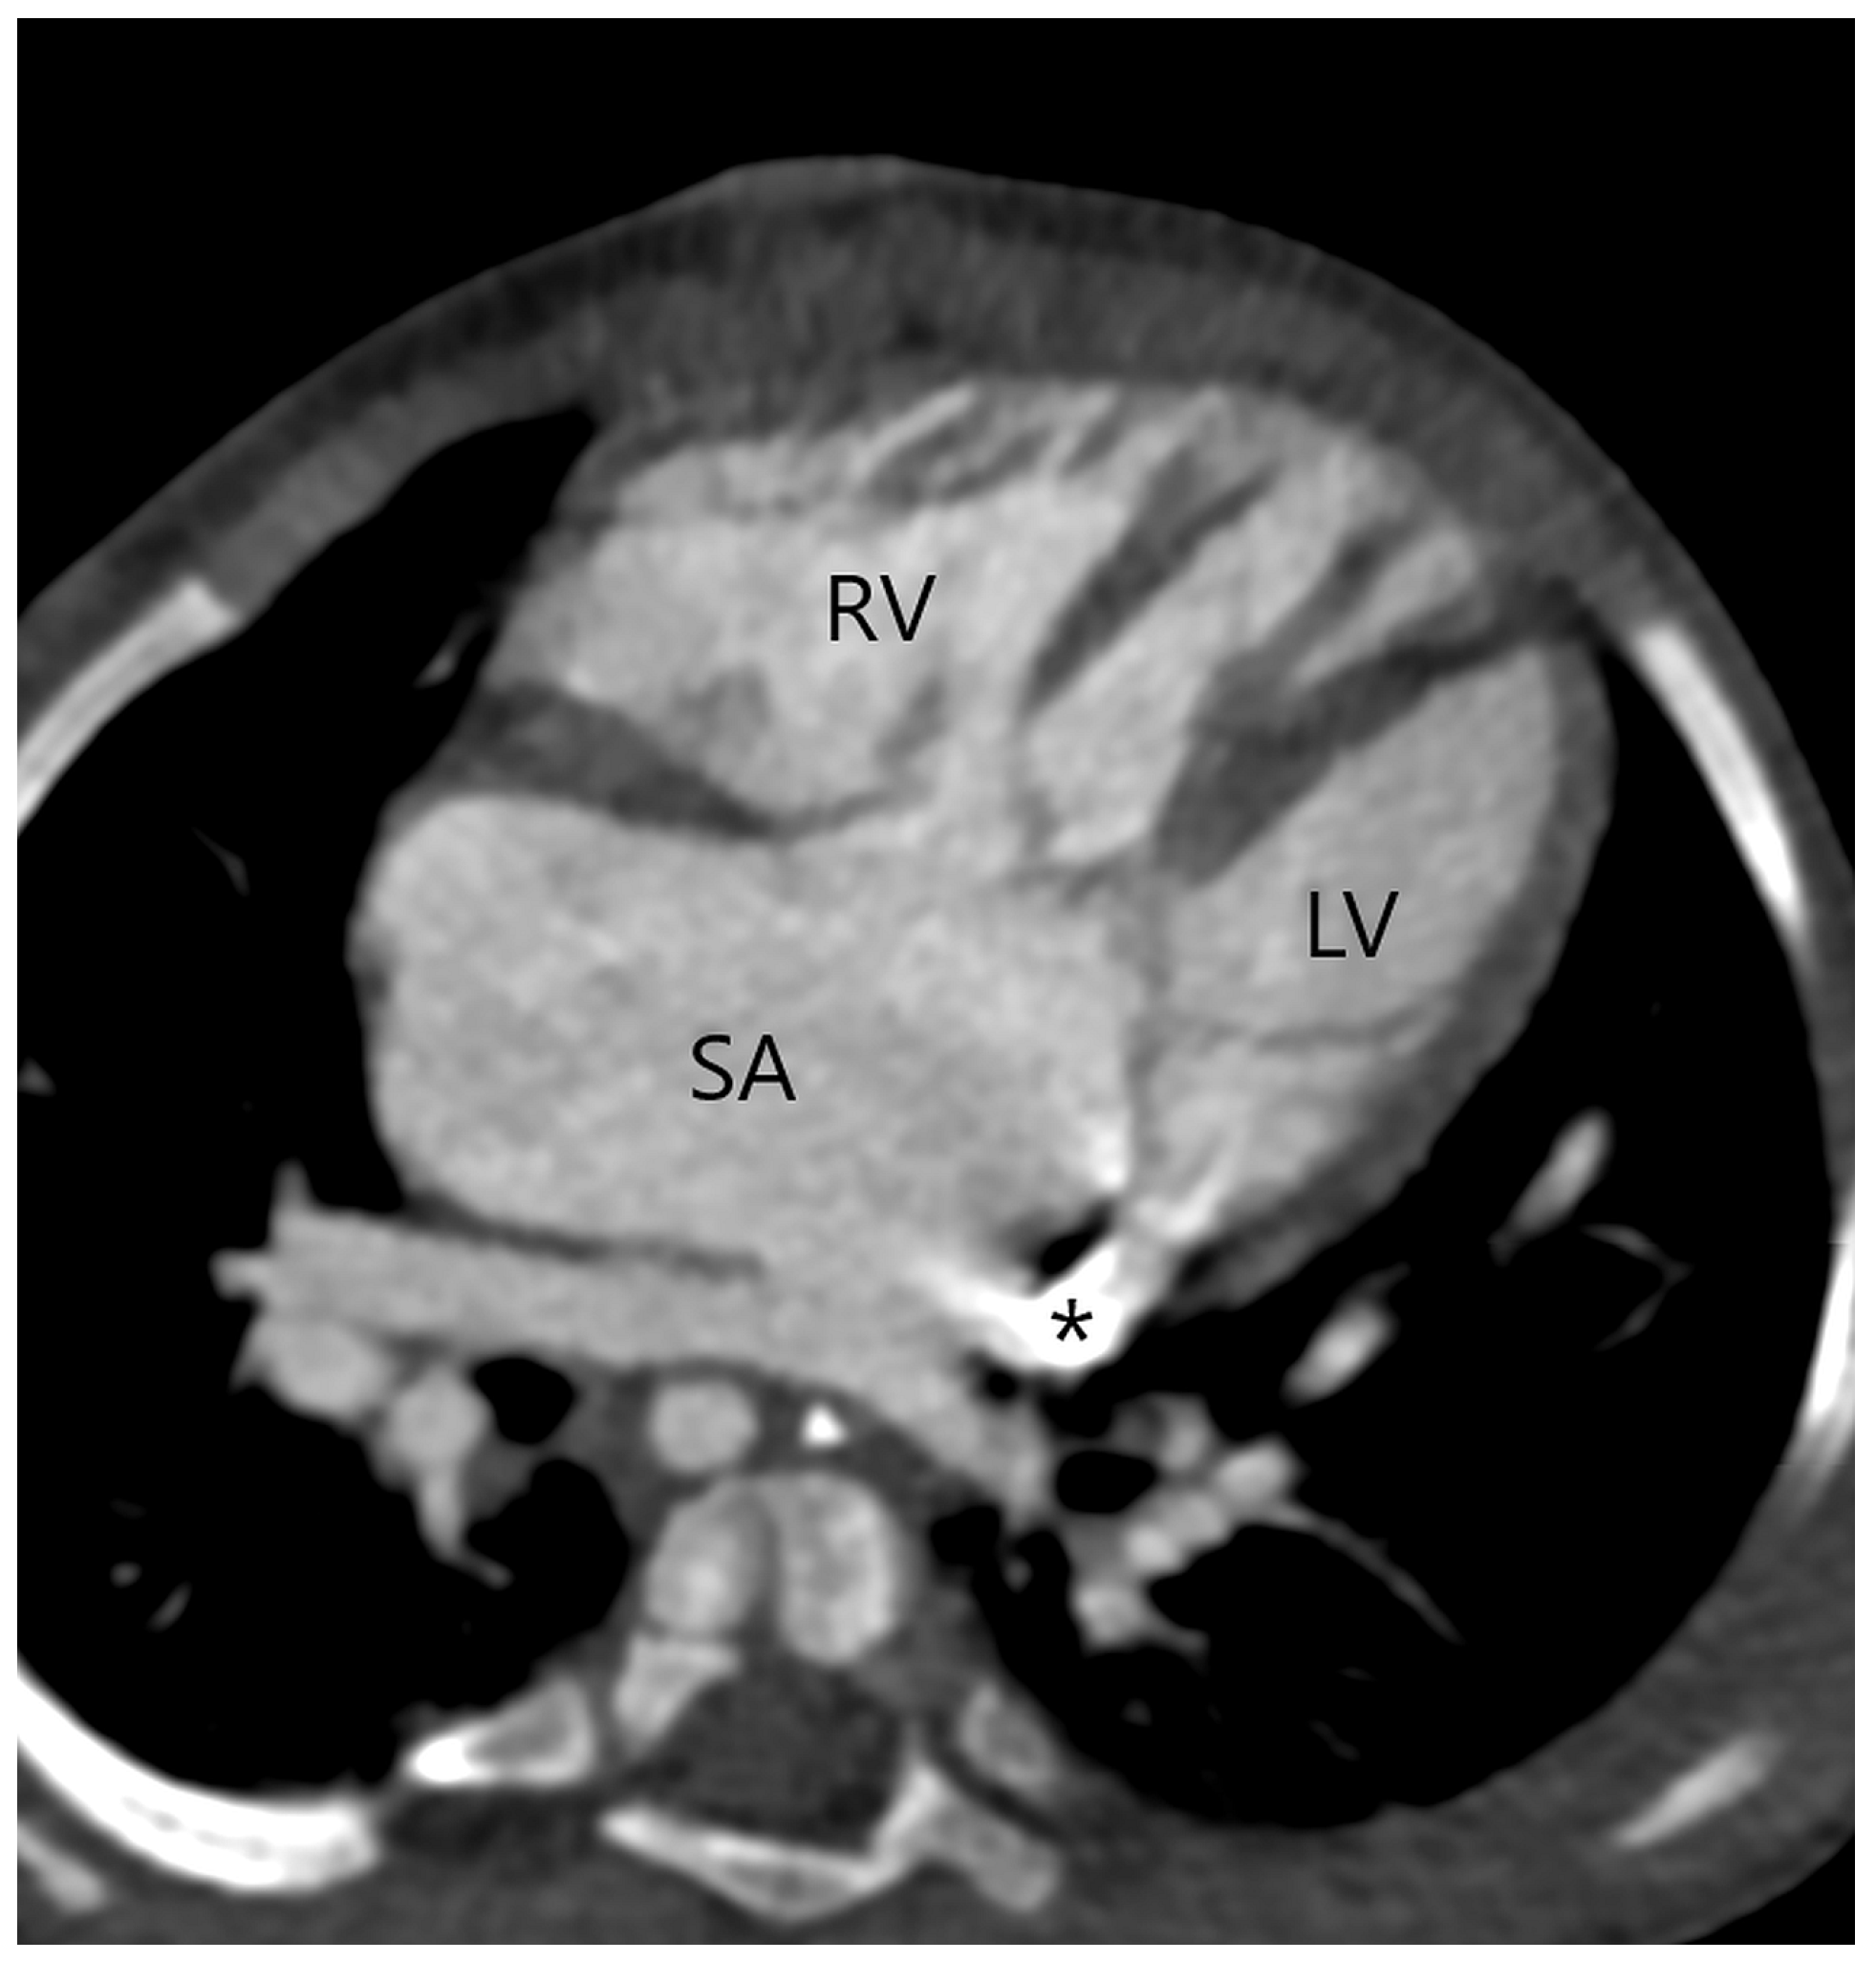

Figure 5.

A single atrium (SA) with a complete atrioventricular septal defect in a patient with a type 1 APW. A persistent left superior vena cava is draining into the coronary sinus (asterisk). Right ventricle (RV); left ventricle (LV).